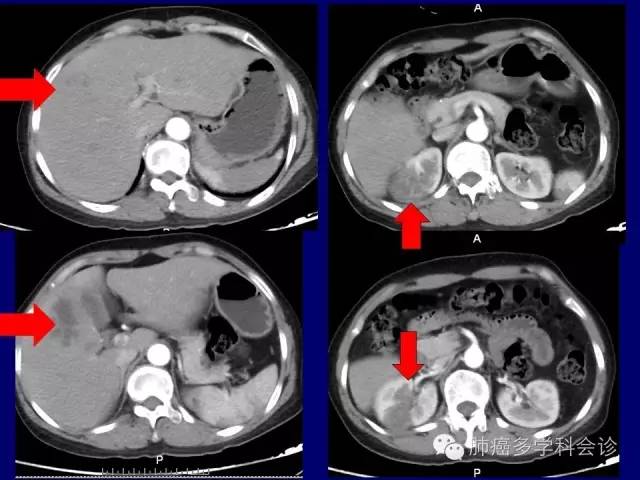

肿瘤与血栓的关系,ALK阳性NSCLC易发生广泛而严重血栓?

高凝状态,多发血栓的诊断和治疗(小分子肝素使用);